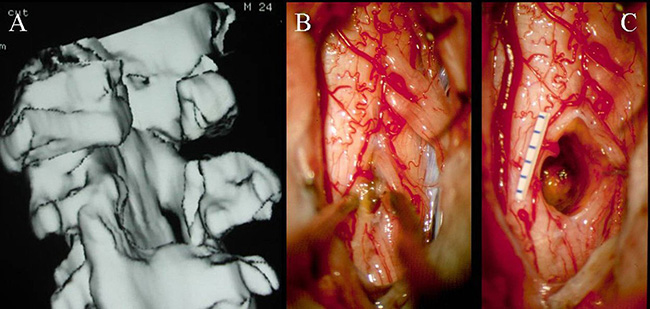

(A-C)3D-CT扫描显示位于C1-2水平的髓内CM的术后图像。(B)在术中脊髓表面观察到含铁血黄素染色。(C)完全切除髓内CM,显示髓鞘切开的程度

巴特朗菲教授指出,显微镜可用来顺利地进行髓内手术切除,当创口较小化并且在精确的肿瘤位置进行切除时,这些损伤通常不会在切除期间出血。术中神经监测对神经外科医生有很大帮助,使其能够更精确地操作并且术后神经功能缺损的风险更低。由于髓内海绵状血管瘤通常位于脊髓的背面,因此,我们证明术中SSEP监测是监测此病手术中脊髓完整性的可靠手段。